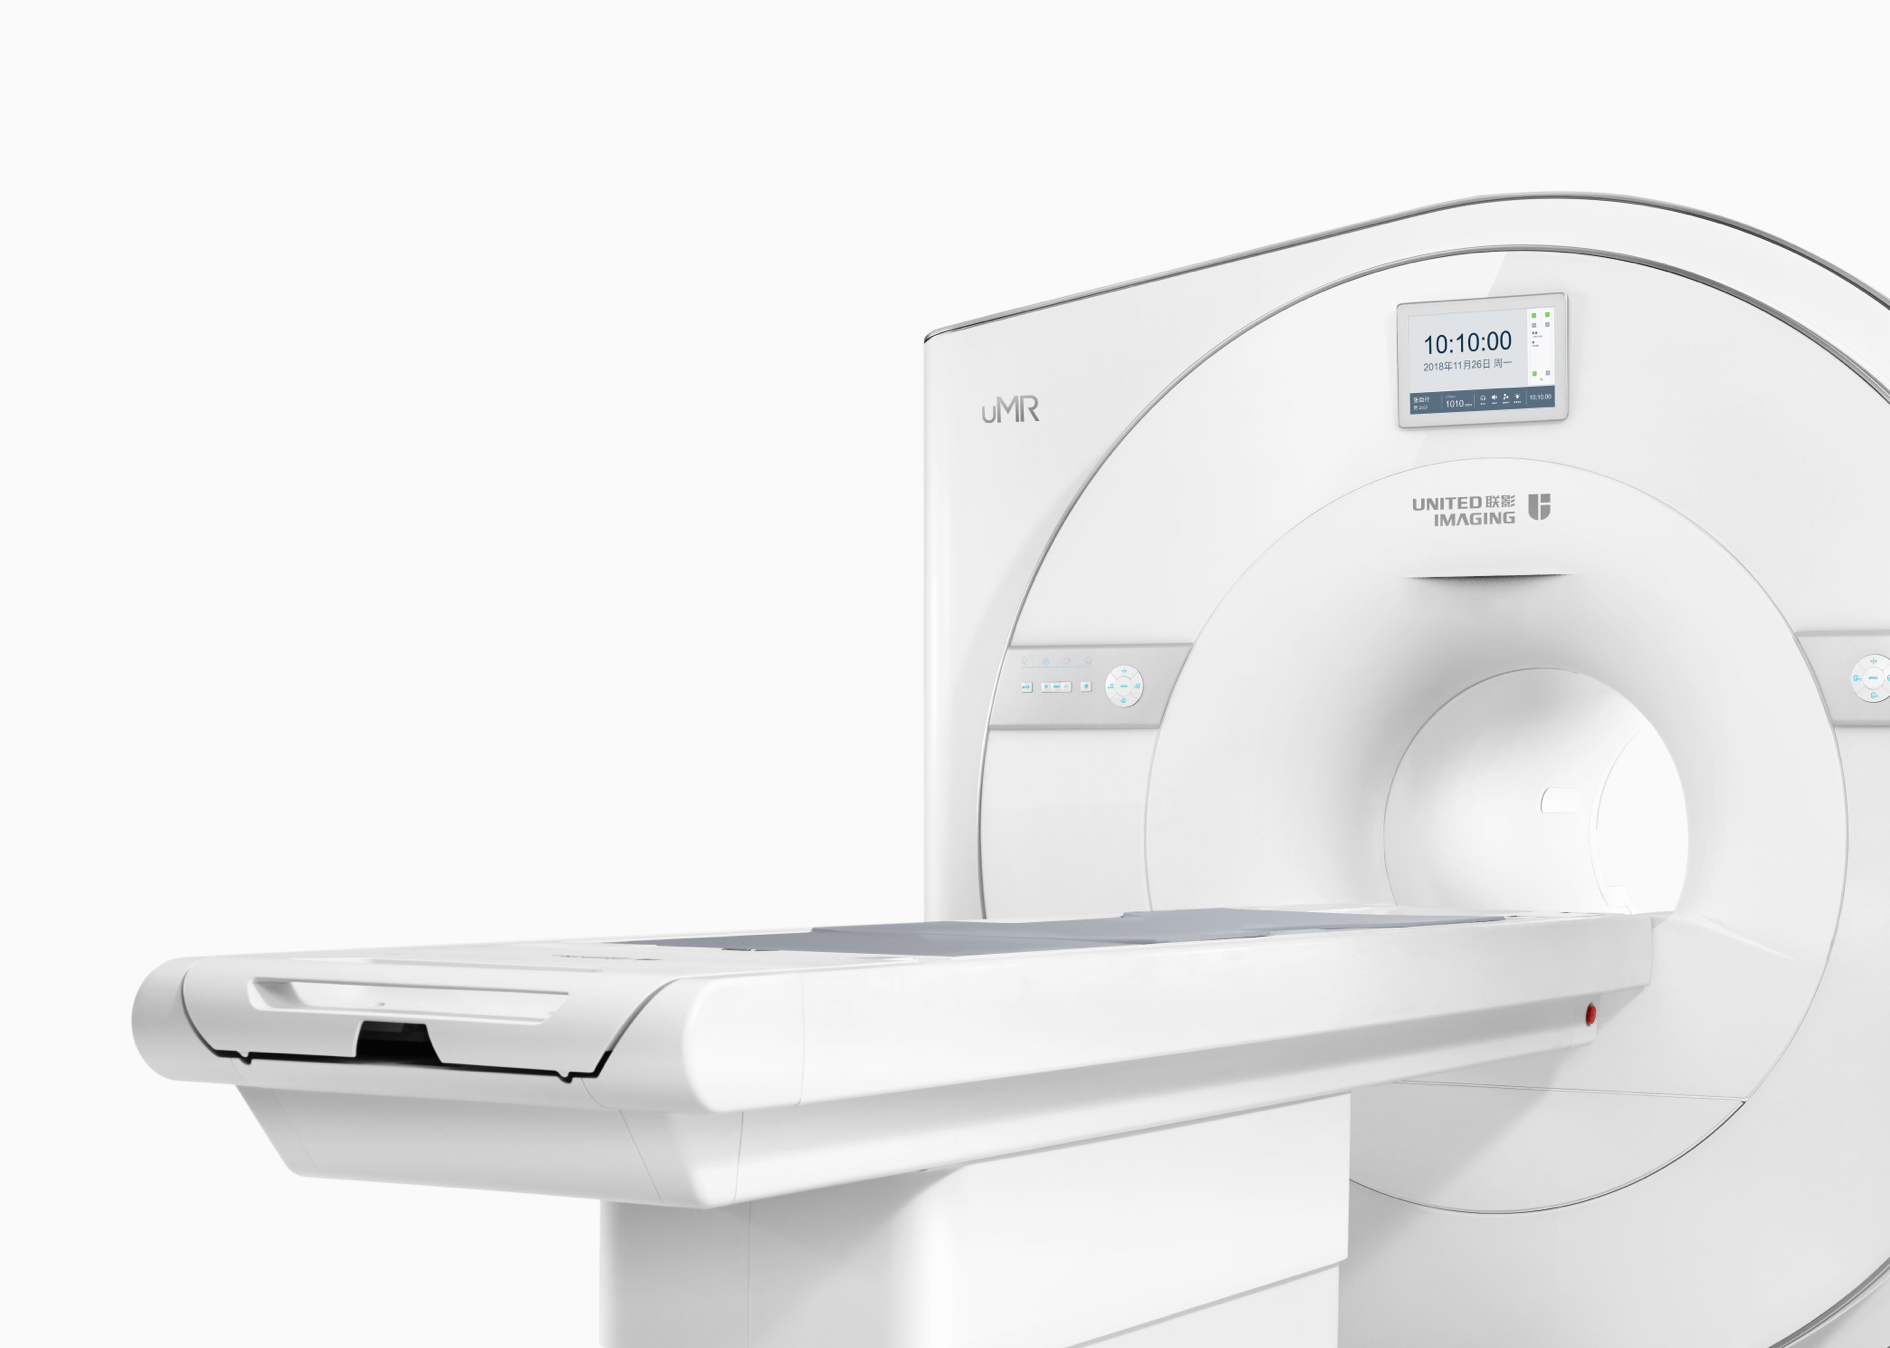

智云磁体

自主研发的匀场技术,优异的磁场均匀度。

智云梯度

智能涡流补偿技术,高梯度性能。